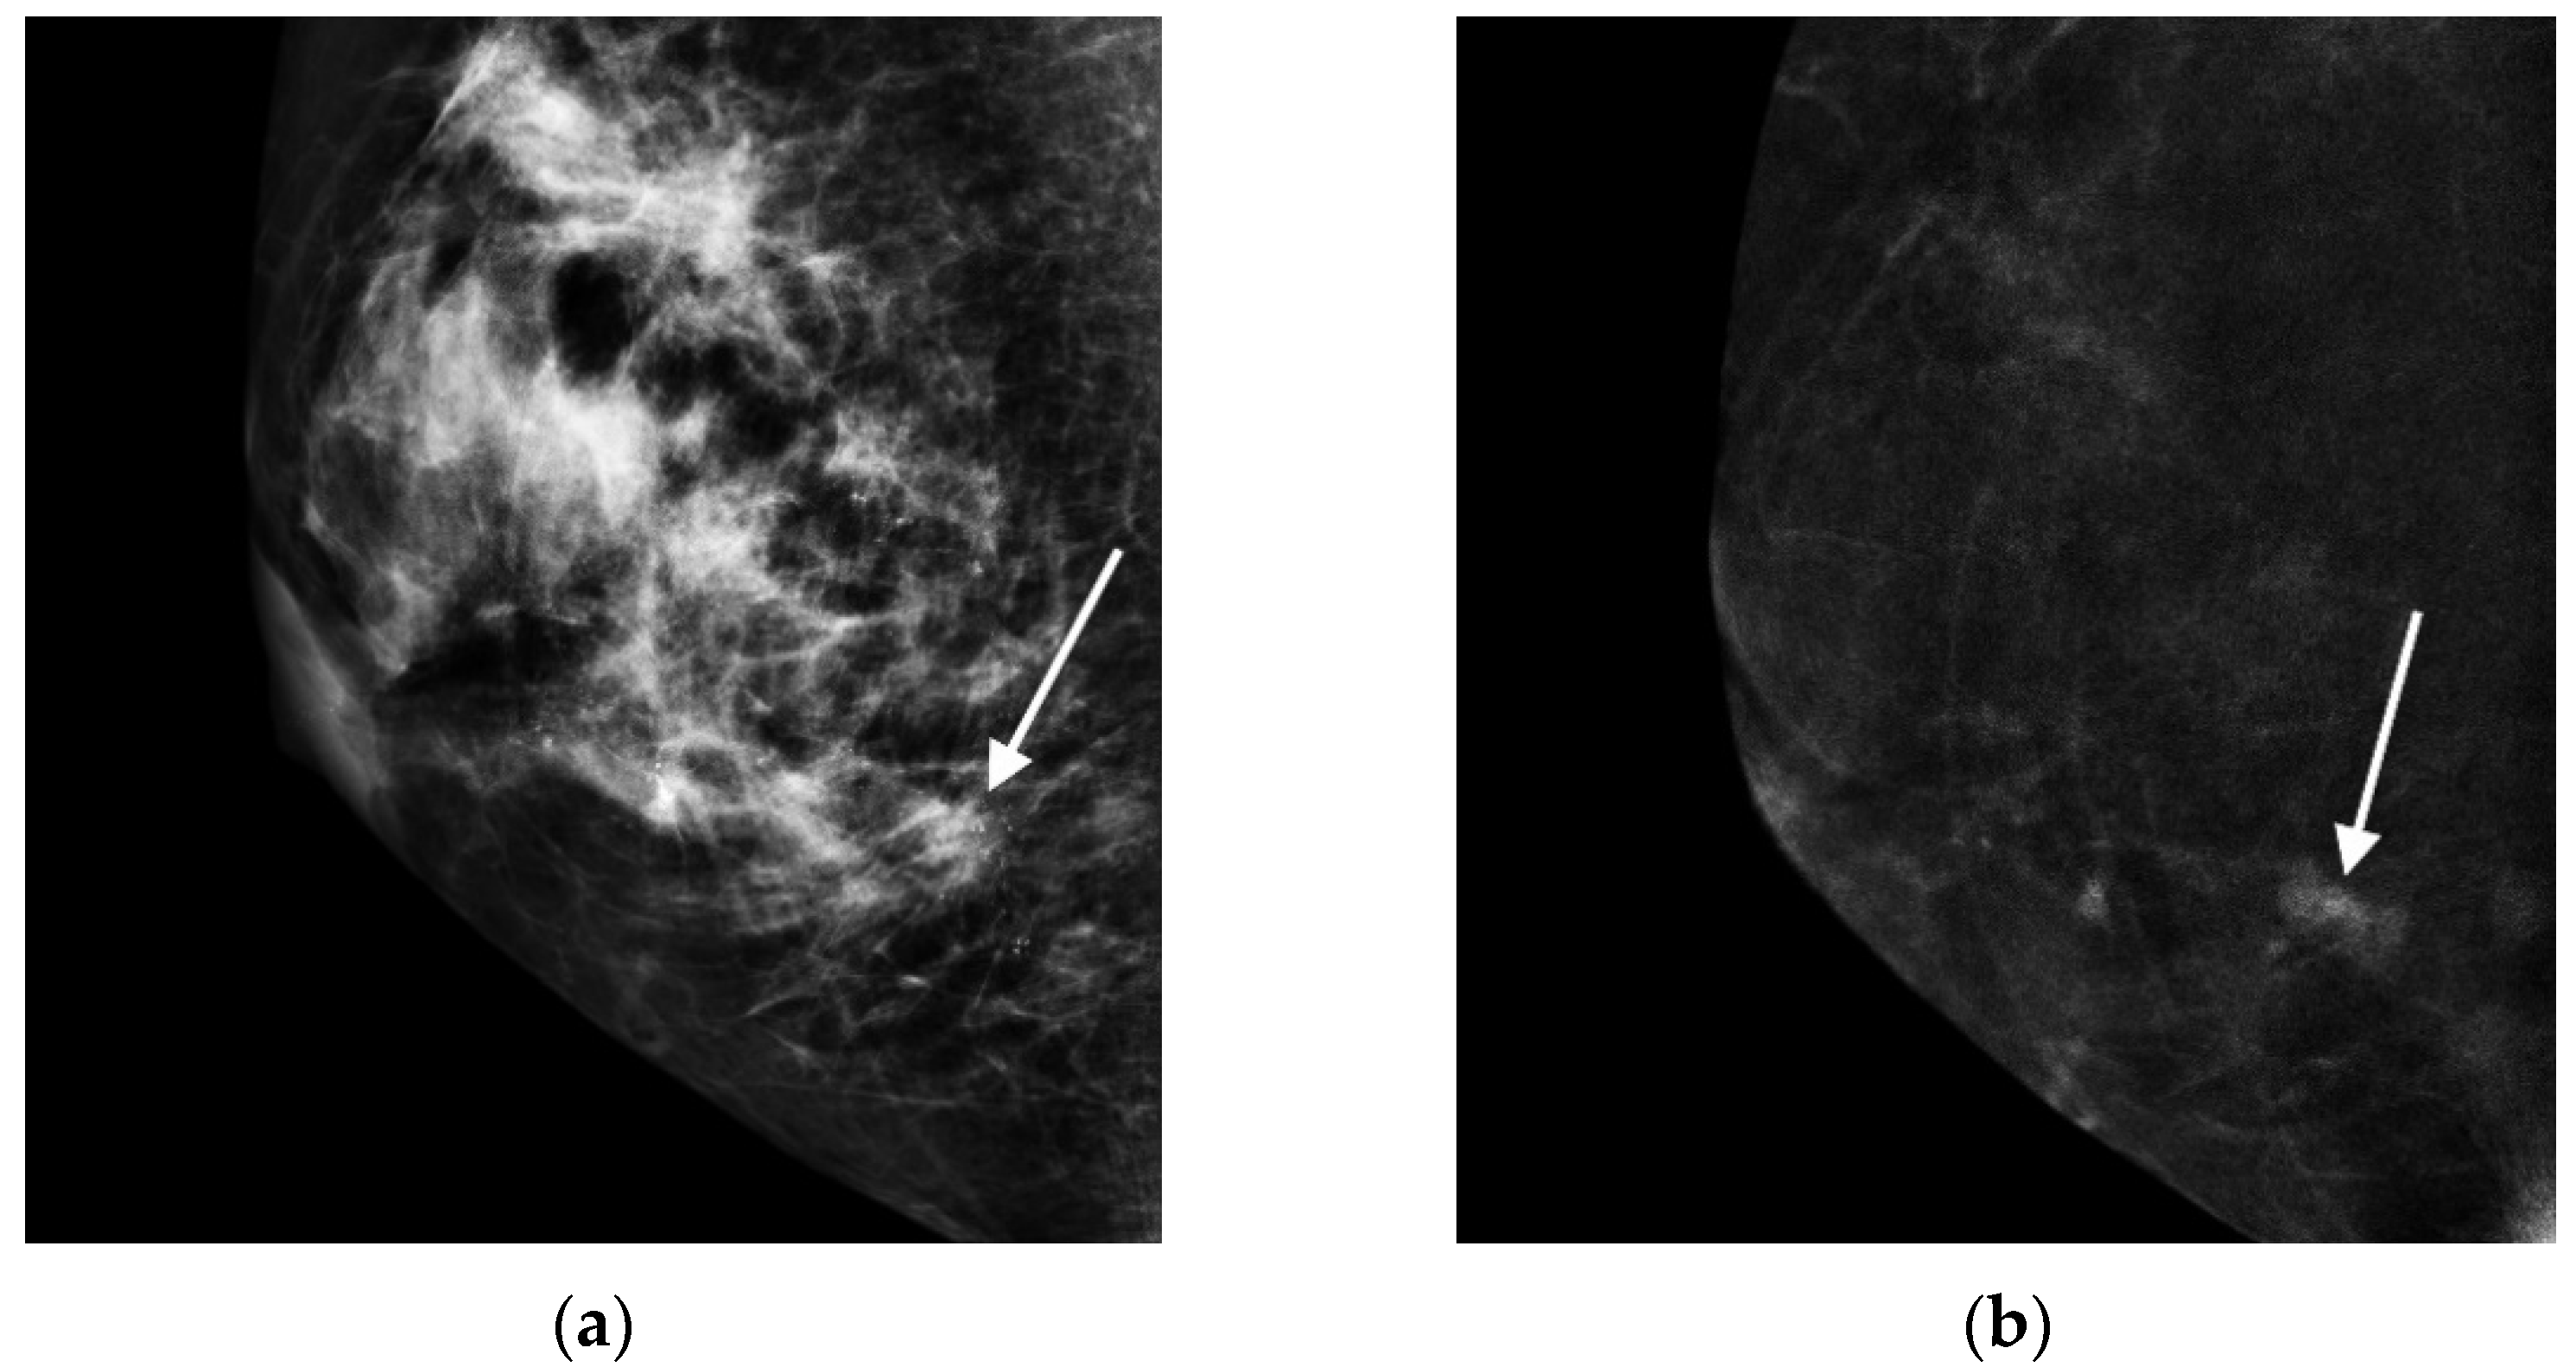

- Cheung, Y.C.; Juan, Y.H.; Lin, Y.C.; Lo, Y.F.; Tsai, H.P.; Ueng, S.H.; Chen, S.C. Dual-Energy Contrast-Enhanced Spectral Mammography: Enhancement Analysis on BI-RADS 4 Non-Mass Microcalcifications in Screened Women. PLoS ONE 2016, 11, e0162740. [Google Scholar]

- Houben, I.P.; Vanwetswinkel, S.; Kalia, V.; Thywissen, T.; Nelemans, P.J.; Heuts, E.M.; Smidt, M.L.; Meyer-Baese, A.; Wildberger, J.E.; Lobbes, M. Contrast-enhanced spectral mammography in the evaluation of breast suspicious calcifications: Diagnostic accuracy and impact on surgical management. Acta Radiol. 2019, 60, 1110–1117. [Google Scholar] [CrossRef] [Green Version]

- Long, R.; Cao, K.; Cao, M.; Li, X.T.; Gao, F.; Zhang, F.D.; Yu, Y.Z.; Sun, Y.S. Improving the Diagnostic Accuracy of Breast BI-RADS 4 Microcalcification-Only Lesions Using Contrast-Enhanced Mammography. Clin. Breast Cancer 2021, 21, 256–262. [Google Scholar] [CrossRef] [PubMed]